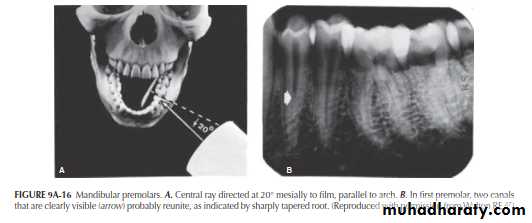

Mandibular Premolars

The importance of varying the horizontal angulation for mandibular premolars is demonstrated in Figure 9A-15A. The central beam is directed at a right angle to the film. What appears to be a single straight canal is discernible in each premolar (Figure 9A-15B).Mandibular Premolars

There is an indication, however, in the image of the first premolar that the canal might bifurcate at the point of the abrupt change (“fast break”) in density (arrow). Directing the central ray 20° from the mesial in the first premolar (Figure 9A-16A) causes the bifurcation to separate into two canals (Figure 9A-16B). The tapering outline of the tooth, seen in both projections, would indicate, on the other hand, that the two canals undoubtedly rejoin to form a common canal at the apex. In both the right-angle and 20° variance projections, the second premolar appears as a single canal.Maxillary Molars